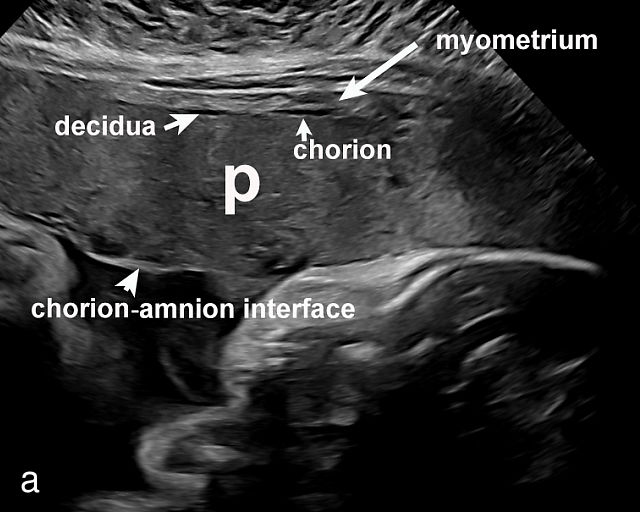

- The uterine wall (myometrium) and the decidua/chorion interface – The outermost layer, the uterine wall or myometrium, appears as a gray area with varying thickness (Figure 2a) depending on placental location. The myometrium is generally thicker when the placenta is located in the upper uterus or fundus. Just beneath the myometrium lies the decidua, a hypoechoic (black) layer where the spiral arteries develop.

- The amnion–chorion (or chorion–amnion) interface – The amnion, the innermost fetal membrane, is more echogenic and appears as a gray line, while the underlying chorion is slightly less echogenic. This interface is important for identifying abnormalities in the fetal surface of the placenta.

- The placental body – The main mass of the placenta, where most abnormalities are detected. The texture, thickness and uniformity of the placental body should be carefully examined for any irregularities.

- The umbilical cord insertion (Figure 2b,c) and placental margin (Figure 2d) – Special attention should be paid to the site at which the umbilical cord or vessels insert into the placenta, as well as the marginal regions of the placenta, to identify potential abnormalities.

(a) Transabdominal grayscale ultrasound image of the placenta showing the four key placental regions: the myometrium (gray area), decidua (black line), chorion (light gray thin line), placental body (p), and the chorion–amnion interface. (b) Grayscale ultrasound image of the umbilical cord insertion into the placenta. (c) Same view as in (b) but with color Doppler applied. (d) Normal placental edge (arrow), which is a common location for placental lakes. (e) Rolled placental edges (arrows) in circumvallate placenta (p).